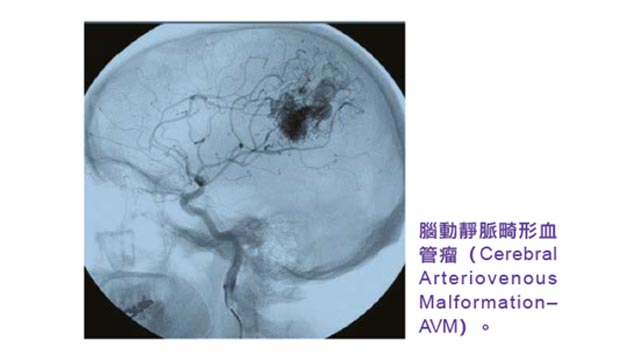

其後的腰椎磁共振造影只顯示退化性腰椎病,只能解釋她背痛症狀,但並不能解釋右腿麻痺無力的原因。於是陳小姐接受了進一步的磁力共振檢查,但覆蓋範圍只延伸到頸椎和胸椎,可是卻未有發現。最後患者終於接受了醫生原先的全中樞神經系統磁力共振的建議,進行了剩下來的腦部及腦血管磁力共振檢查。腦部磁共振影像最終發現了病因,就是患者左邊腦部裏有一個先天性的腦動靜脈畸形血管瘤,並有破裂出血的現象,血塊壓迫着左邊腦部負責控制右腿的神經,因而導致陳小姐右腿麻痺無力。

於是醫生為陳小姐進行了微創開顱手術,利用導航系統及術中持續監測腦功能系統,在顯微鏡下醫生小心翼翼地把血塊取出,為陳小姐腦部進行減壓,同時把腦動靜脈畸形血管瘤切除。手術後,患者的右腿力度回復正常,可正常行走,其後和兒子移居到澳洲生活,多年來活動如常。